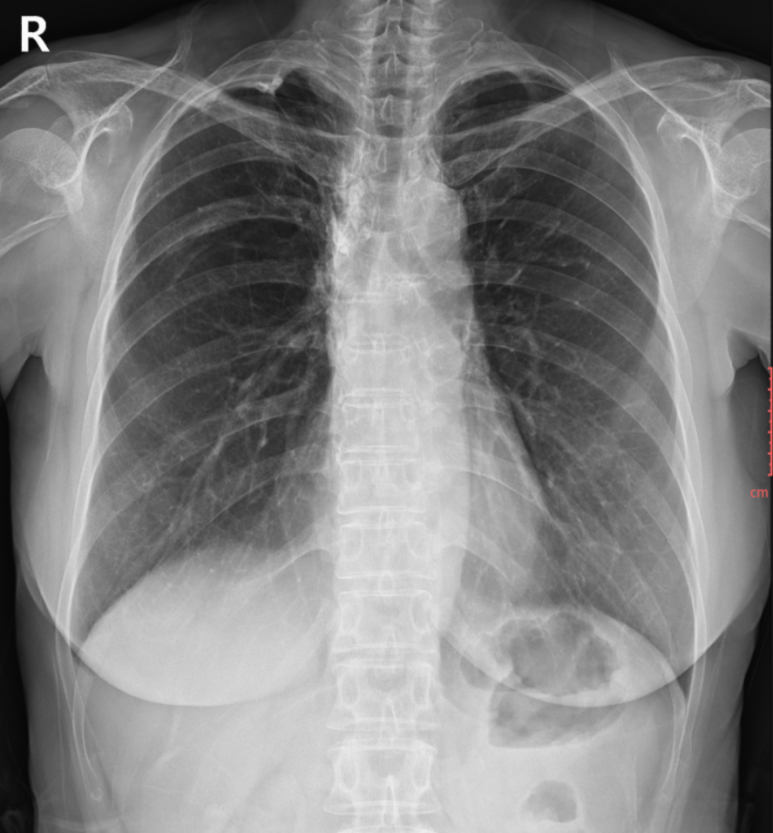

1. 흉부 X‑ray

X‑ray 폐 이상 없음. 심장초음파에서 승모판막 두 부위의 역류 확인으로 폐쇄부전증을 확인하였고, 혈액검사에서 심부전 수치 상승한 것을 고려하여 심장판막 질환으로 인한 호흡곤란 증상으로 사료되어 약물치료 개시 및 추적.

• X‑ray: 폐 이상 없음 X‑ray: 폐 이상 없음